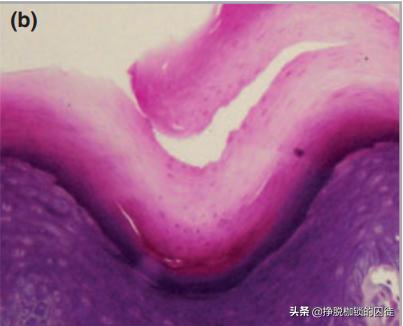

后来,有的医生通过显微镜观察发现,问题主要出在皮肤的角质层的中层出现分离,不涉及真皮层。

基于此,早在1919年就有医生给起了一个新的名字,叫“分离性角质剥脱”,直到今天仍被医学界广泛接受。

因此,分离性角质剥脱脱下的都是很薄的一层表皮,脱皮后的下层虽然有点“嫩”,感觉上有些敏感,但仍是具有完整角质层的皮肤,因而并不会有其他问题,也不需要进行任何治疗,一般经过2、3个月后就会自己消失。